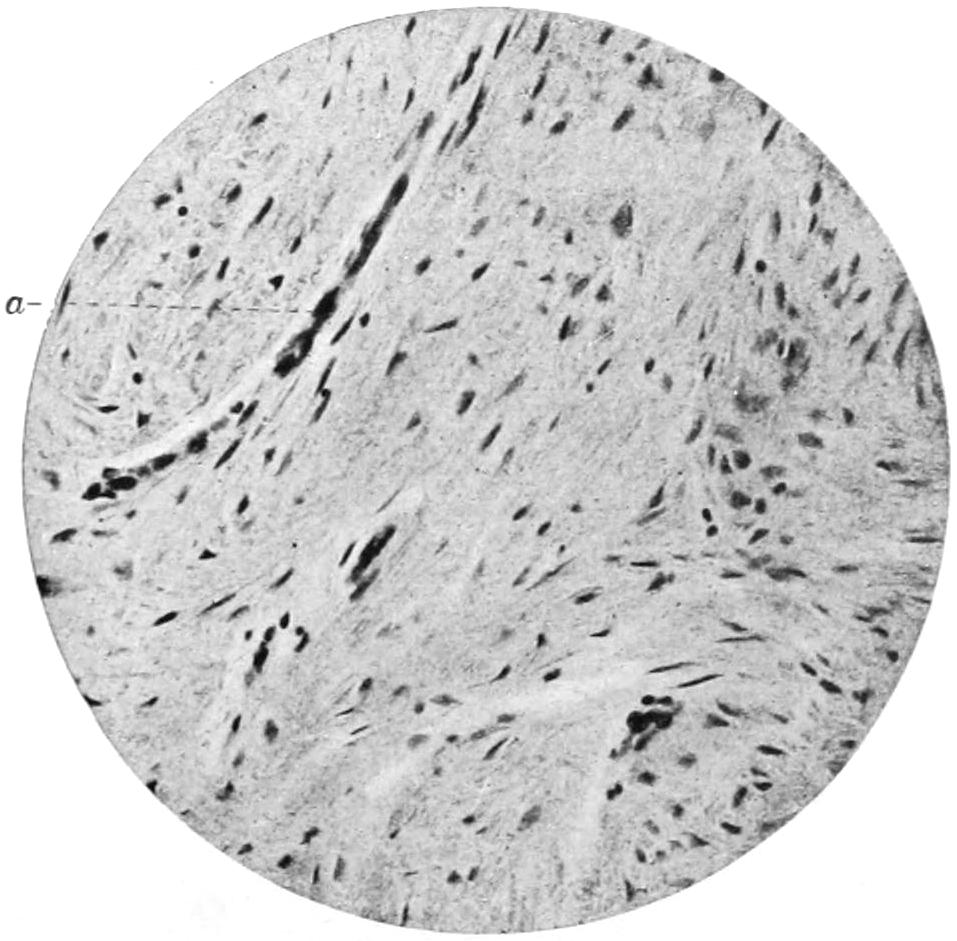

PLATE I

PLATE I.

BLOOD.

(Ehrlich triple stain.)

(Prepared by Dr. I. P. Lyon.)

Fig. I. TYPES OF LEUCOCYTES.

a. Polymorphonuclear Neutrophile. b. Polymorphonuclear Eosinophile. c. Myelocyte (Neutrophilic). d. Eosinophilic Myelocyte. e. Large Lymphocyte (large Mononuclear). f. Small Lymphocyte (small Mononuclear).

Fig. II. NORMAL BLOOD.

Field contains one neutrophile. Reds are normal.

Fig. III. ANÆMIA, POST-OPERATIVE (secondary).

The reds are fewer than normal, and are deficient in hæmoglobin and somewhat irregular in form. One normoblast is seen in the field, and two neutrophiles and one small lymphocyte, showing a marked post-hæmorrhagic anæmia, with leucocytosis.

Fig. IV. LEUCOCYTOSIS, INFLAMMATORY.

The reds are normal. A marked leucocytosis is shown, with five neutrophiles and one small lymphocyte. This illustration may also serve the purpose of showing the leucocytosis of malignant tumor.

Fig. V. TRICHINOSIS.

A marked leucocytosis is shown, consisting of an eosinophilia.

Fig. VI. LYMPHATIC LEUKÆMIA.

Slight anæmia. A large relative and absolute increase of the lymphocytes (chiefly the small lymphocytes) is shown.

Fig. VII. SPLENO-MYELOGENOUS LEUKÆMIA.

The reds show a secondary anæmia. Two normoblasts are shown. The leucocytosis is massive. Twenty leucocytes are shown, consisting of nine neutrophiles, seven myelocytes, two small lymphocytes, one eosinophile (polymorphonuclear) and one eosinophilic myelocyte. Note the polymorphous condition of the leucocytes, i. e., their variations from the typical in size and form.

Fig. VIII. VARIETIES OF RED CORPUSCLES.

a. Normal Red Corpuscle (normocyte). b, c. Anæmic Red Corpuscles. d-g. Poikilocytes. h. Microcyte. i. Megalocyte. j-n. Nucleated Red Corpuscles. j, k. Normoblasts. l. Microblast. m, n. Megaloblasts.

The value of a careful blood examination is well illustrated by Plate I, prepared by Dr. Irving P. Lyon, in which are displayed the alterations of greatest interest to the surgeon.